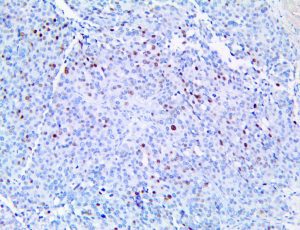

It is the ICU physician who is most likely to witness one of the deadliest manifestations of the abnormal immunological response, the cytokine storm syndrome (CSS). This response is also referred to by some as the cytokine release syndrome (CRS). CSS is characterized by continuous activation and expansion of macrophage and lymphocyte populations, which secrete large amounts of cytokines, causing the cytokine storm. This massive cytokine release is akin to hemophagocytic lymphohistiocytosis (HLH) disease, a syndrome characterized by initial unchecked and persistent activation of cytotoxic T lymphocytes and NK cells.

Clinical and laboratory manifestations of HLH include fever, enlarged liver and/or spleen, neurologic dysfunction, coagulopathy, liver dysfunction, cytopenias (i.e., low levels of erythrocytes, leukocytes, and/or platelets), hypertriglyceridemia, hyperferritinemia, hemophagocytosis, and eventually diminished NK cell activity as the immune system becomes progressively paralyzed. HLH can be familial (primary HLH) or secondary to another disease process (sHLH), such as rheumatic disease, in which it is referred to as macrophage activation syndrome (MAS, characterized by elevated ferritin).